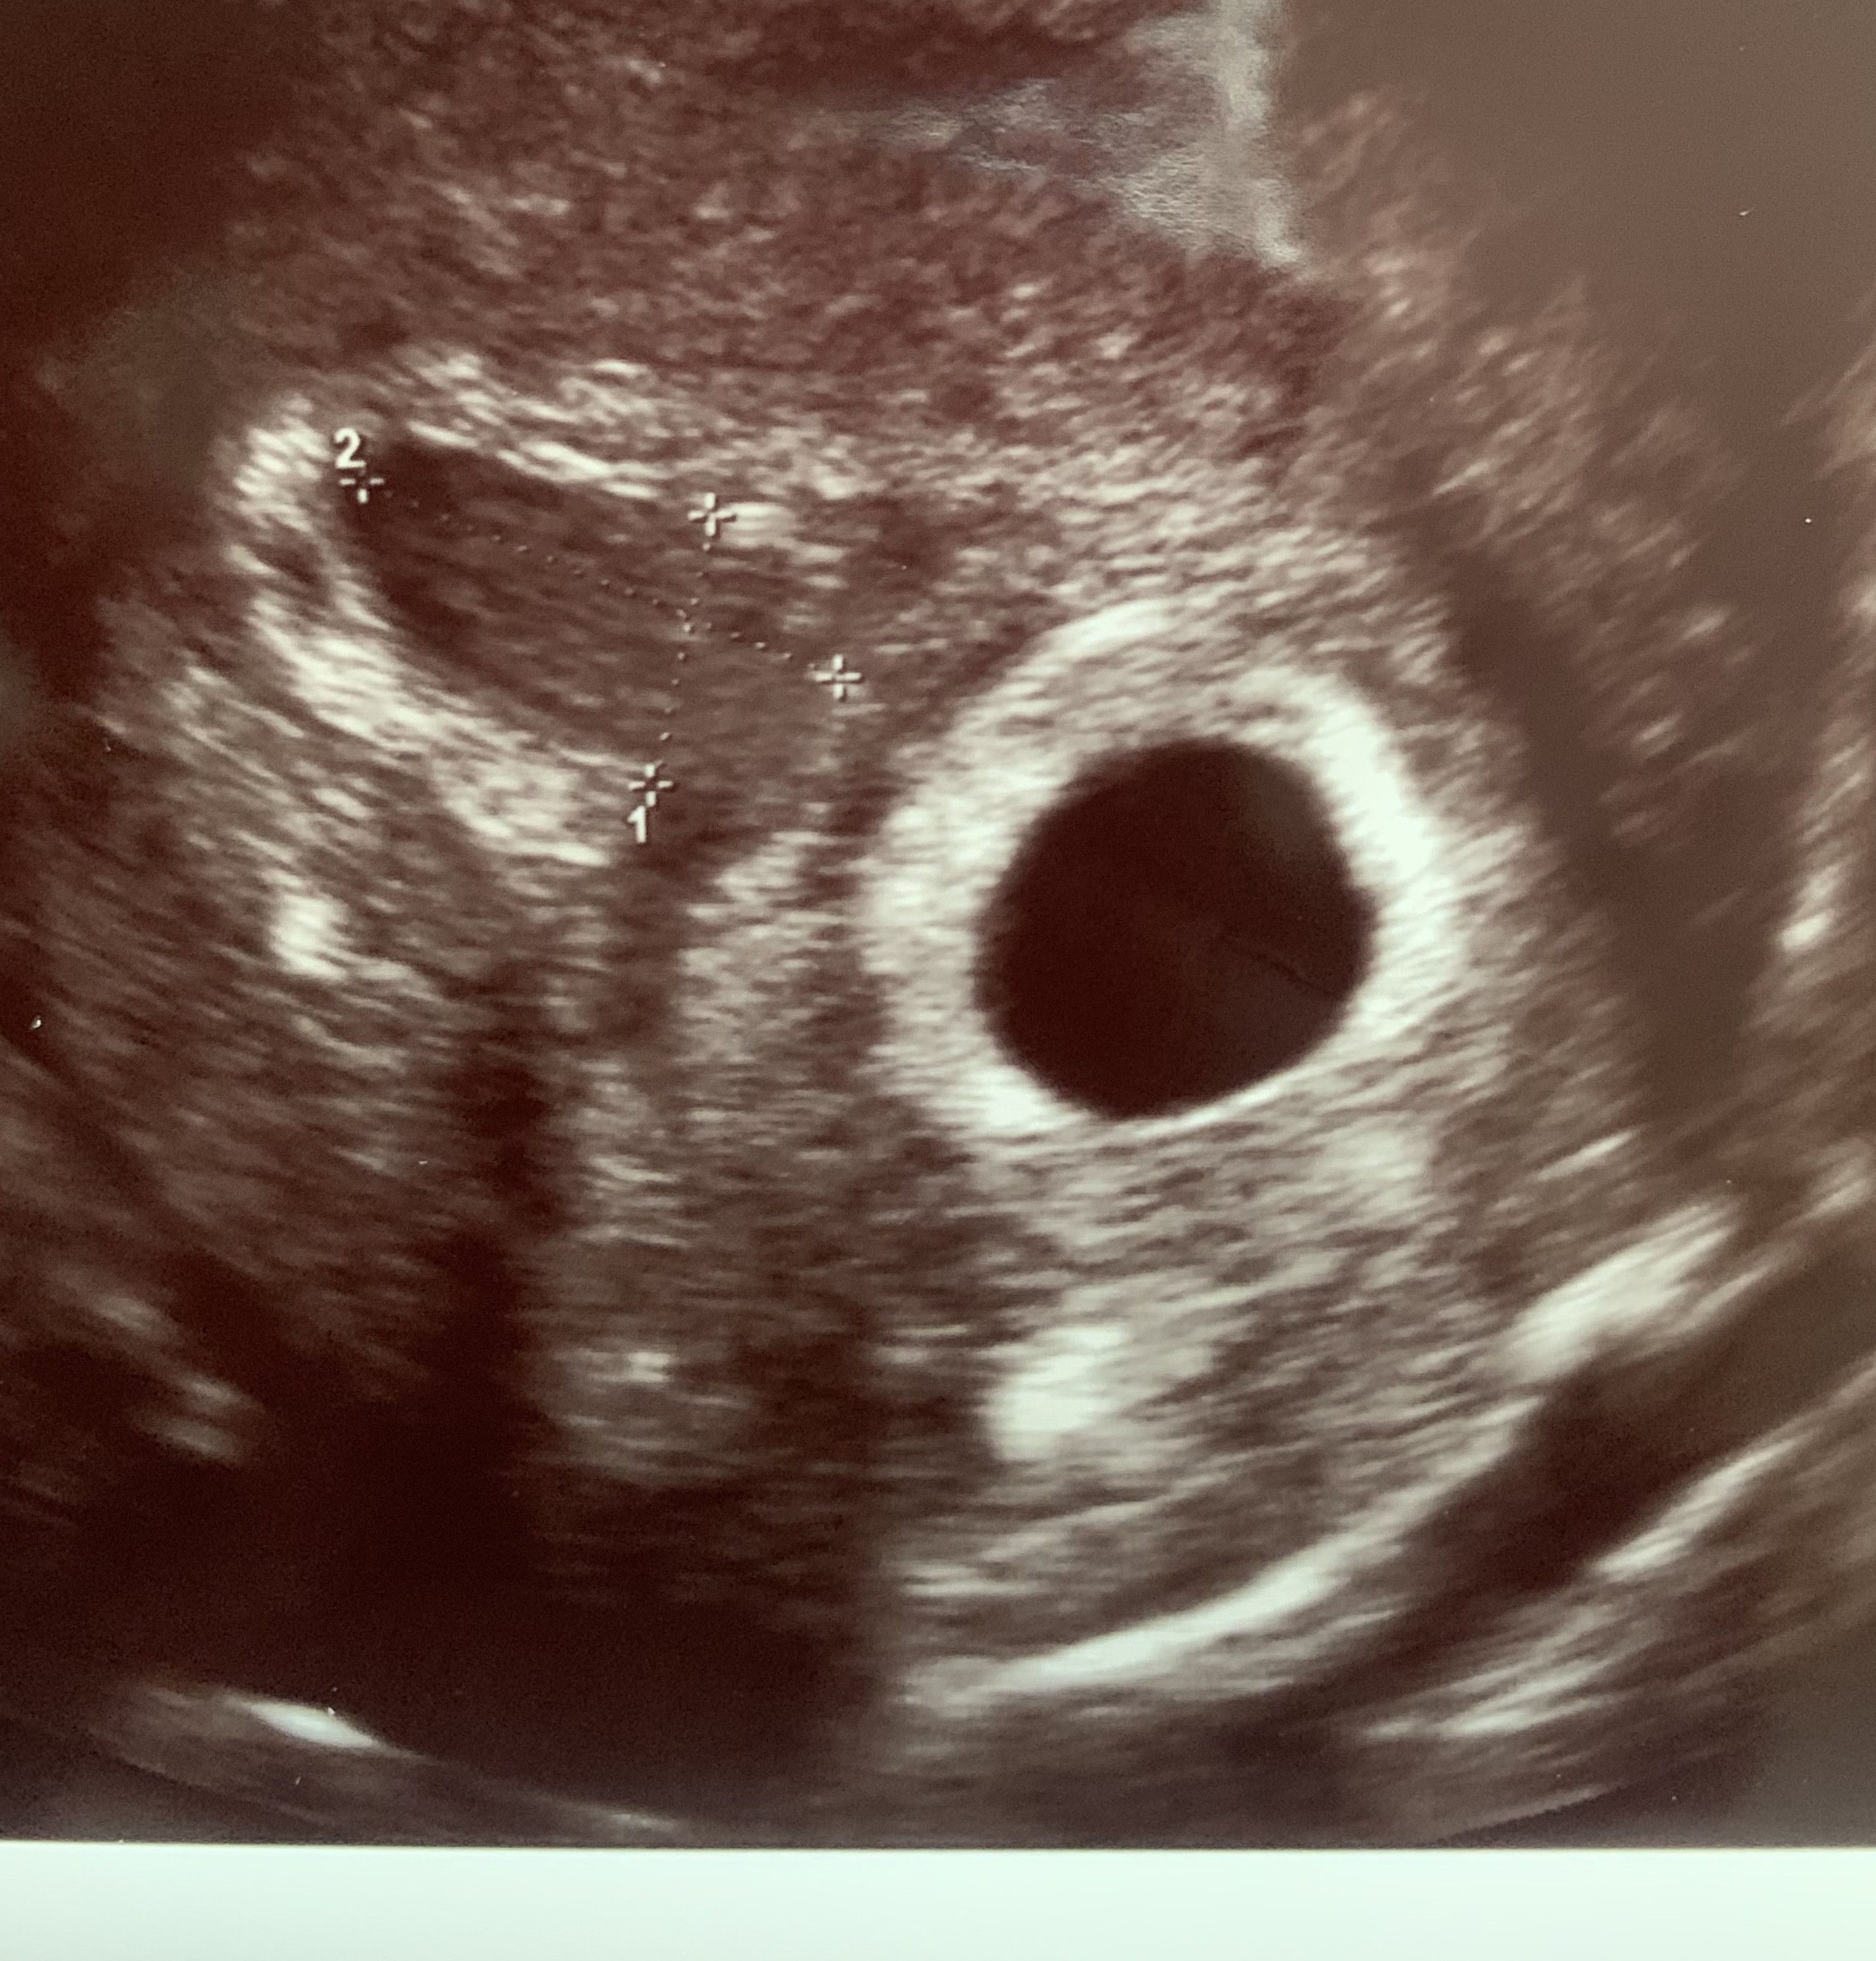

0,7x1,27 cm; wrzucam zdjęcieNajważniejsze że z Maluszkiem wszystko dobrze! Krwiaki się wchłaniaja, trzeba się tej myśli trzymać. A jak duży jest?

Załączniki